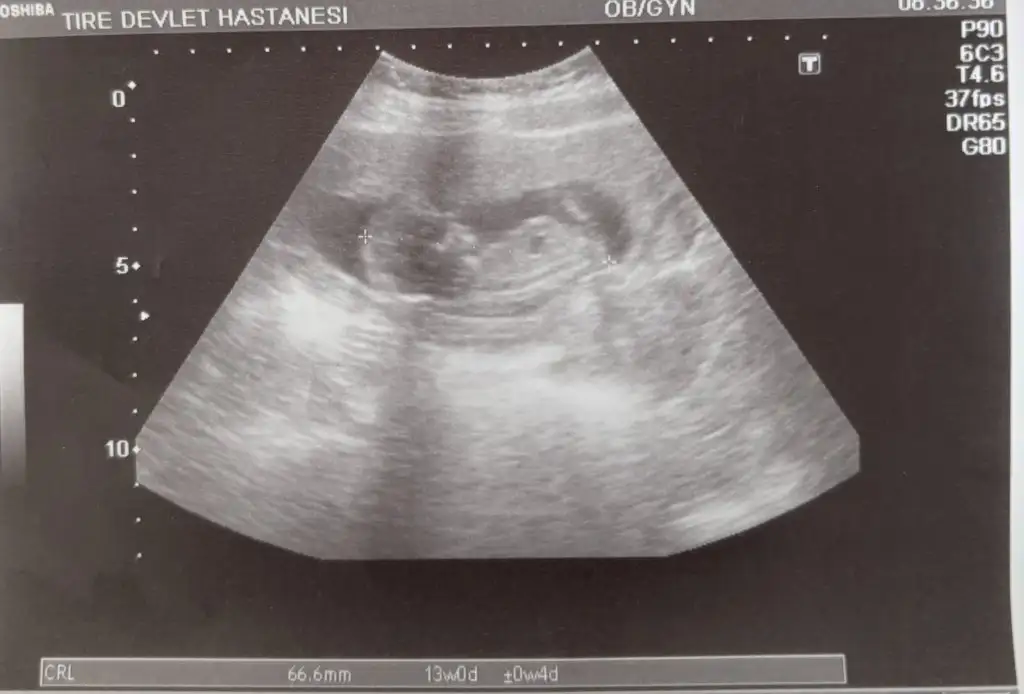

Bizim de bakar mısınız 10+1 bugün

• IMG_1404.webp

IMG_1404.webp

28,6 KB · Görüntüleme: 66

• IMG_1405.webp

IMG_1405.webp

41,6 KB · Görüntüleme: 69